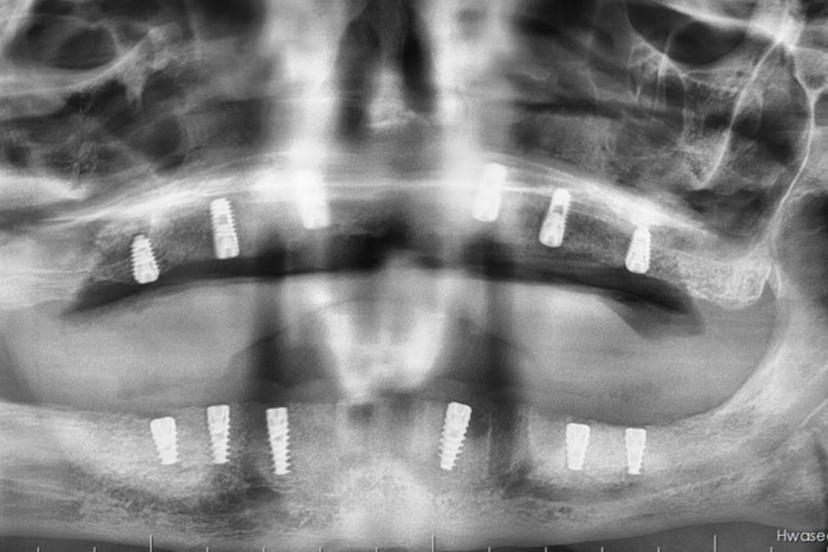

Batman Ağız ve Diş Sağlığı Hastanesi’nde ileri cerrahi gerektiren bir vakada, genel anestezi altında açık sinüs lift (eksternal sinüs lift) ameliyatı ile birlikte implant uygulaması yapıldı.

Hastanede tedavi gören 55 yaşındaki Hüsnü Üner’de sağ ve sol üst çene arka bölgelerinde ileri düzey sinüs sarkması ve kemik yetersizliği tespit edildi. Lokal anestezi ile tedavi edilmesi mümkün olmayan vakada, Ağız, Diş ve Çene Cerrahisi Uzmanı Uzm. Dt. Ebru Baydan Çol tarafından genel anestezi altında her iki üst çeneye aynı seansta açık sinüs lift ameliyatı uygulandı.

Cerrahi işlemin ardından hastanın üst ve alt çenesine implantlar yerleştirildi. Ameliyat sonrası genel durumu stabil olan hastanın iyileşme sürecinin planlandığı şekilde devam ettiği bildirildi.